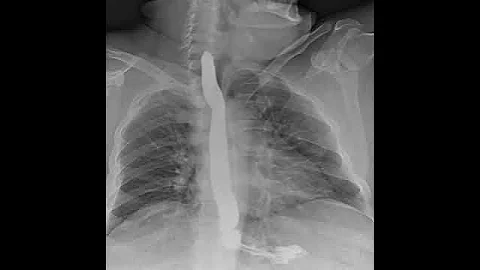

Dynamic X-ray Retrospective View Of The Esophagus In Motion | Konica Minolta Healthcare

Experience the incredible detail of Dynamic Digital Radiography (DDR) technology as we take a Retrospective look at the ...